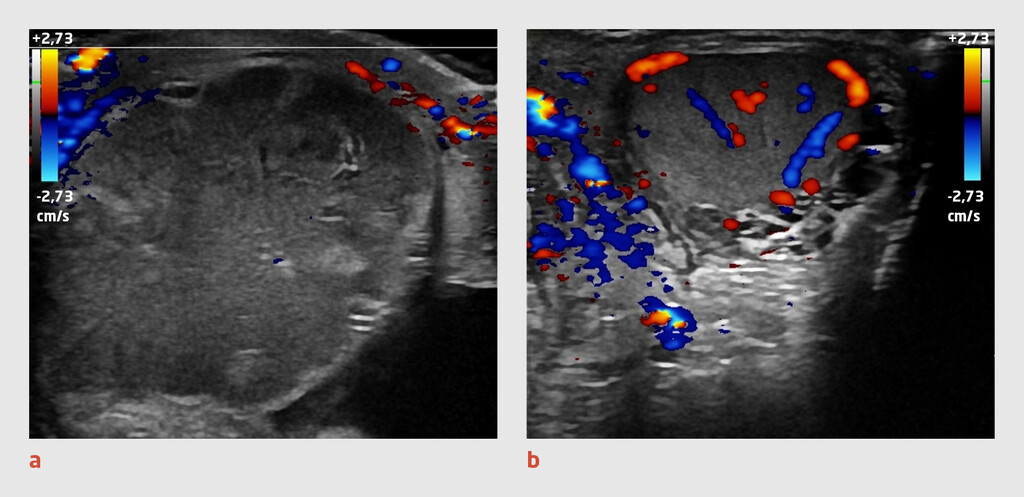

In deze klinische les beschrijven wij de casus van een gezonde, 16-jarige jongeman met een torsio testis die zeer kort na een doorgemaakte epididymitis ontstaat. Met deze les illustreren wij hoe belangrijk het is om de diagnose ‘epididymitis’ te heroverwegen bij patiënten bij wie het scrotum opnieuw pijnlijk wordt. Wanneer een torsio testis in een vroeg stadium wordt herkend en behandeld, is er een grotere kans op behoud van de testis en de fertiliteit.1,2

Patiënt, een gezonde, 16-jarige jongeman, komt op de Spoedeisende Hulp, omdat zijn rechter hemiscrotum sinds 2 dagen pijnlijk en gezwollen is. Hij gebruikt geen medicatie. Bij aankomst op de SEH geeft patiënt aan dat de pijn inmiddels is afgenomen, maar dat de zwelling persisteert. Hij heeft geen buikpijn gehad, is niet ziek geweest en heeft niet gebraakt. Ook heeft hij geen mictie- of defecatieklachten. Patiënt is niet seksueel actief.

Bij lichamelijk onderzoek zien wij een niet-zieke, adequate patiënt met een helder bewustzijn. Bij palpatie van de linker testis voelen wij een ronde, elastische, gladde en regelmatige testis; de epididymis kan goed worden onderscheiden van de testis. Patiënt geeft geen pijn aan tijdens het onderzoek van het linker hemiscrotum. Bij palpatie van de rechter testis voelen wij een elastische, onregelmatige zwelling; testis en epididymis zijn ditmaal niet goed van elkaar te onderscheiden. De rechter epididymis is gevoelig. Differentiaaldiagnostisch denken wij aan…

In deze klinische les wordt een tevoren gezonde, 16-jarige jongeman beschreven met een sedert twee dagen pijnlijk gezwollen rechter hemiscrotum. Gezien leeftijd en anamnese, was de diagnose torsio testis wel zeer waarschijnlijk. Omdat de pijn afgezakt was, was er waarschijnlijk sprake van òf necrose òf een detorsie. Gezien de beschreven goede doorbloeding van de rechter testis en epididymis bij echografie, was er vermoedelijk sprake van een status na detorsie. Het ontbreken van de cruciale echografische afbeelding  van deze rechter testis, maakt deze klinische les niet echt sterker. De radioloog heeft vermoedelijk zuiver op het echografisch beeld gevaren, en kliniek en leeftijd onvoldoende betrokken in zijn conclusie, vandaar de onjuiste diagnose van epididymitis. De clinicus heeft deze diagnose helaas overgenomen, en de patiënt is met pijnstillers naar huis gestuurd. Zes dagen later is er vermoedelijk weer een torsio opgetreden die uiteindelijk twee dagen later echografisch en later bij operatie bevestigd werd, de testis was toen niet meer te redden. De lezer blijft in verwarring achter als de auteurs aan het eind concluderen dat er sprake moet zijn geweest van een nieuw ontstane torsio testis in het verloop van een acute  epididymitis. Eens te meer geldt: “Eine Krankheit genügt”